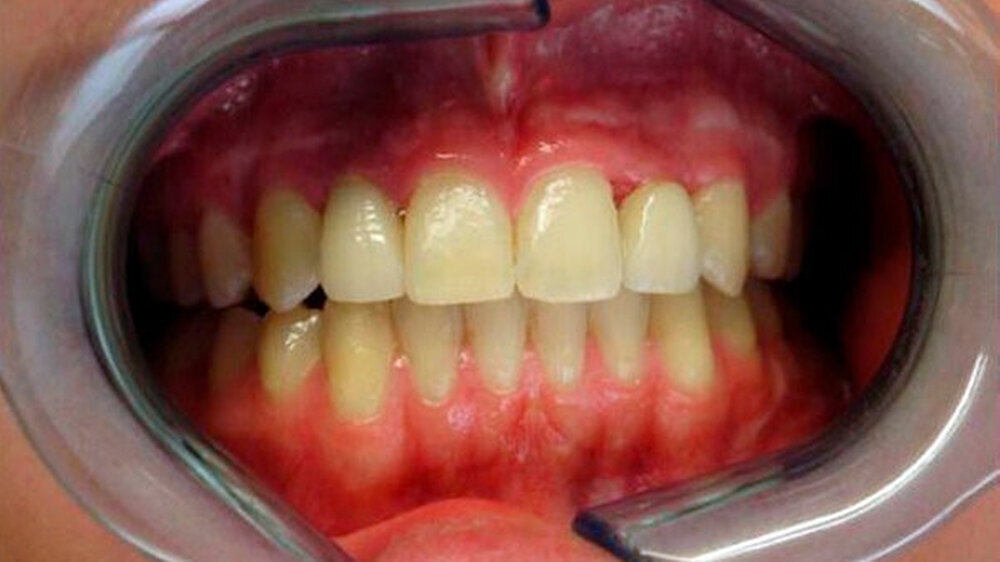

Nach Abschluss der operativen Versorgung begann am siebten postoperativen Tag die eigentliche orthodontische Phase. Etwa fünf Monate später wurden nach Lückenöffnung die Implantate regio 12 und 22 inseriert und die Distraktionsosteogenese des Unterkiefers durchgeführt. Eine direkte prothetische Versorgung des Zapfenzahns 12 war nicht möglich - auch hier erfolgte die Implantatinseration. Im weiteren Behandlungsverlauf wurden die Distraktoren nach zirka sechs Monaten entfernt sowie beide Implantate in üblicher Art und Weise freigelegt und prothetisch versorgt.

Heute, nach zirka eineinhalb Jahren, zeigt sich die Patientin mit der funktionellen und ästhetischen Verbesserung durch die operativen Eingriffe äußerst zufrieden. Sie befindet sich weiterhin in engmaschiger zahnärztlicher/kieferorthopädischer Kontrolle sowie in regelmäßigen Zeitabständen in kieferchirurgischer Nachsorge (Abbildungen 2a bis c).